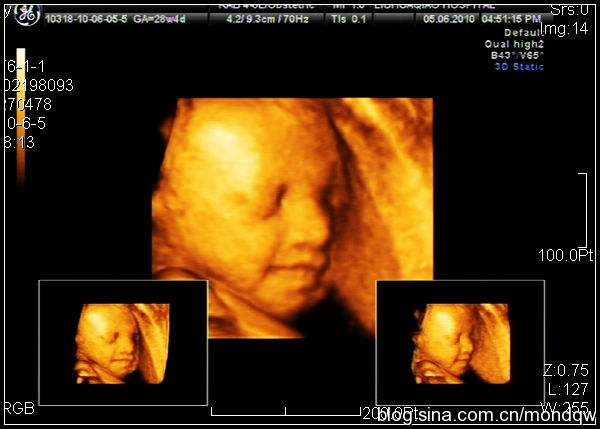

但是很多胎儿在不同时期的检查中,会有脑侧室值大于10mm的情况,具体听听医生的意见,因为在胎儿后期,随着生长,大多能够自己吸收,从而使值变小,隔几周再做b超看看是否继续增宽,